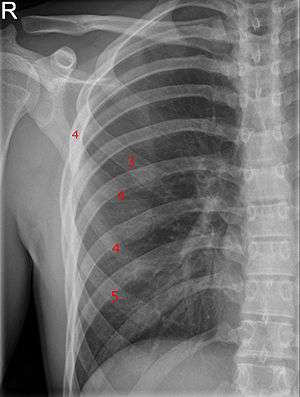

Bifid rib at the right side seen on chest radiograph. The fourth rib splits in two towards the sternal end. | |

A bifid rib (bifurcated rib or sternum bifidum) is a congenital abnormality of the rib cage and associated muscles and nerves which occurs in about 1.2% of humans. Bifid ribs occur in up to 8.4% of Samoans.[1] The sternal end of the rib is cleaved into two. It is usually unilateral.